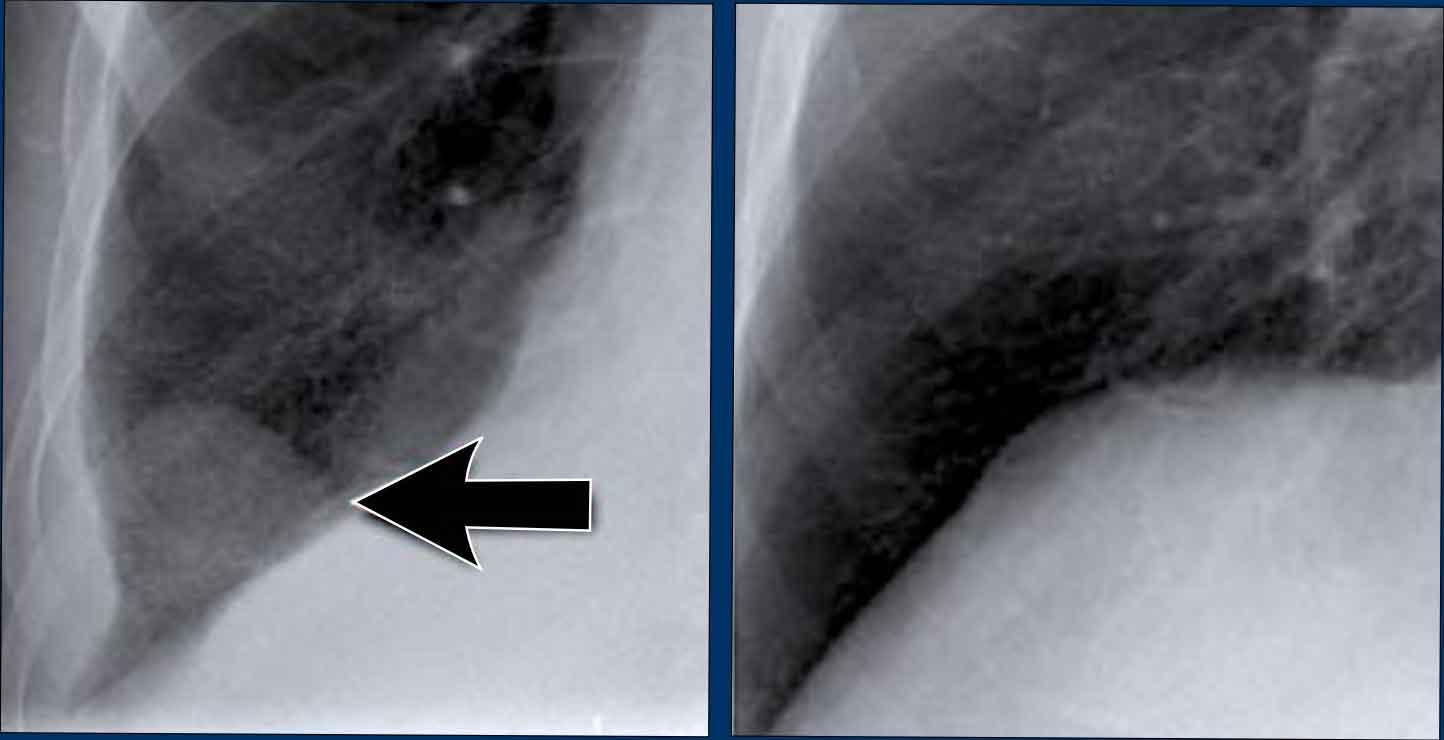

1. Không có dấu hiệu silhouette trong đám đông đặc ở thùy dưới trái (mũi tên xanh dương). 2. Dấu hiệu silhouette trong đám đông đặc ở thùy lưỡi (mũi tên vàng).

Dấu hiệu Silhouette

Dấu hiệu silhouette đề cập đến sự mất đường bờ bình thường giữa các cấu trúc có tỷ trọng X-quang khác nhau, thường gặp nhất là phổi chứa khí tiếp giáp với các cấu trúc phần mềm như tim hoặc cơ hoành.

Dấu hiệu này có vai trò quan trọng trong việc phát hiện các tổn thương kín đáo và định khu tổn thương trong lồng ngực.

Minh họa Dấu hiệu Silhouette

- Không có Dấu hiệu Silhouette (Mũi tên Xanh dương)

- Tâm thất trái, nằm ở phía trước, bình thường được tiếp giáp với thùy lưỡi chứa khí của thùy trên trái.

- Nếu đông đặc xảy ra ở thùy dưới trái (phía sau), ranh giới giữa thùy lưỡi và tim vẫn còn nguyên vẹn, và bờ tim trái được bảo tồn.

- Dấu hiệu Silhouette Dương tính (Mũi tên Vàng)

- Khi đông đặc hiện diện ở thùy lưỡi, vùng này tiếp giáp trực tiếp với bờ tim trái, làm mờ bóng của tâm thất trái.

- Điều này cho thấy tổn thương nằm ở phía trước lồng ngực.

Dấu hiệu Silhouette – Các Ví dụ

Ca lâm sàng 1: Tư thế PA

- Bờ tim trái bị xóa mờ trên phim X-quang tư thế PA.

- Ngay cả khi chưa xem phim nghiêng, dấu hiệu này đã định khu tổn thương ở phân thùy trước của phổi trái, nhiều khả năng là thùy lưỡi.

- Chẩn đoán: Viêm phổi thùy do Streptococcus pneumoniae.

Ca lâm sàng 2: Tư thế PA

- Quan sát thấy đám đông đặc ở thùy dưới trái (mũi tên vàng).

- Bờ tim trái vẫn được xác định rõ với bóng silhouette bình thường (mũi tên xanh dương), cho thấy tổn thương nằm ở phía sau và không liên quan đến thùy lưỡi.